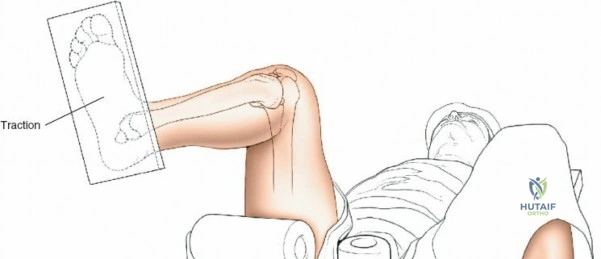

Supine on a Traction Table:

- Setup: The patient is placed supine on a radiolucent operating table. The affected hip is flexed to approximately 60 degrees. A support is strategically placed behind the posterior aspect of the distal thigh to allow the knee to flex freely. Crucially, care must be taken to position this support well away from the popliteal fossa to avoid compression of the popliteal artery and vein, which can lead to neurovascular compromise or compartment syndrome. The knee is then flexed to 100 to 120 degrees. Traction is applied by strapping the patient's foot to the sole plate of the traction apparatus.

- Advantages:

- Provides superior control over fracture reduction, particularly for comminuted or highly unstable patterns, allowing for precise length and alignment restoration.

- Facilitates easier distal locking as the limb is rigidly held.

- Frees up surgical assistants, who are not required to hold the leg.

- Disadvantages:

- Potential for pressure injuries in the popliteal fossa if support is misplaced.

- Risk of compartment syndrome due to prolonged traction.

- Can restrict access to the proximal tibia for very high entry points if knee flexion is insufficient.